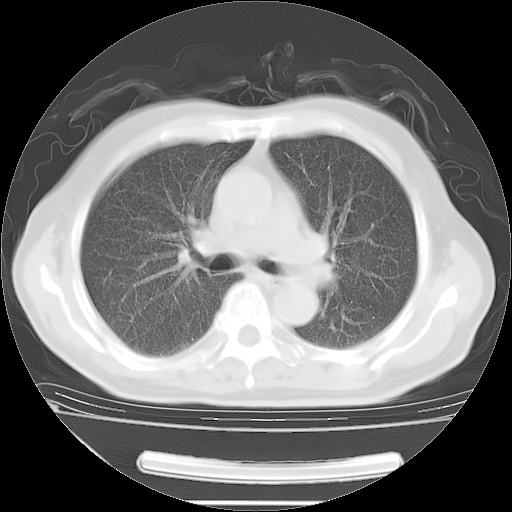

今天复查肺部CT,发现双肺广泛磨玻璃样改变。所以我把3月19日和5月9日相隔50天的肺部CT上传。请大家会诊。

2009年3月19日肺部CT片。

2009年3月19日肺部CT